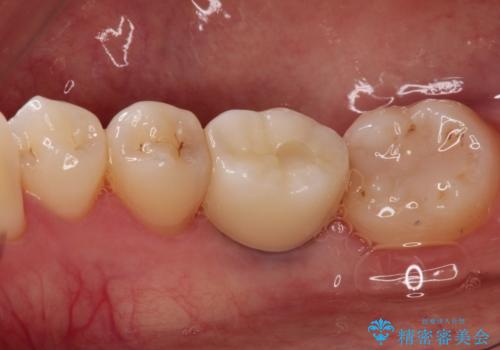

歯並びの改善とインプラントでのかみ合わせの回復 インプラント・セラミック・矯正全顎治療

- 歯医者が怖くて悪い歯をそのままにしてしまった、悪いところを治したいとのことで来院されました。

虫歯の歯や、歯を抜いてしまったところをそのまま放置していたことにより、歯並びも悪くなっていました。

矯正をはじめ、根の治療・インプラント・セラミックによる全体治療を提案させていただき、治療をしていくこととなりました。